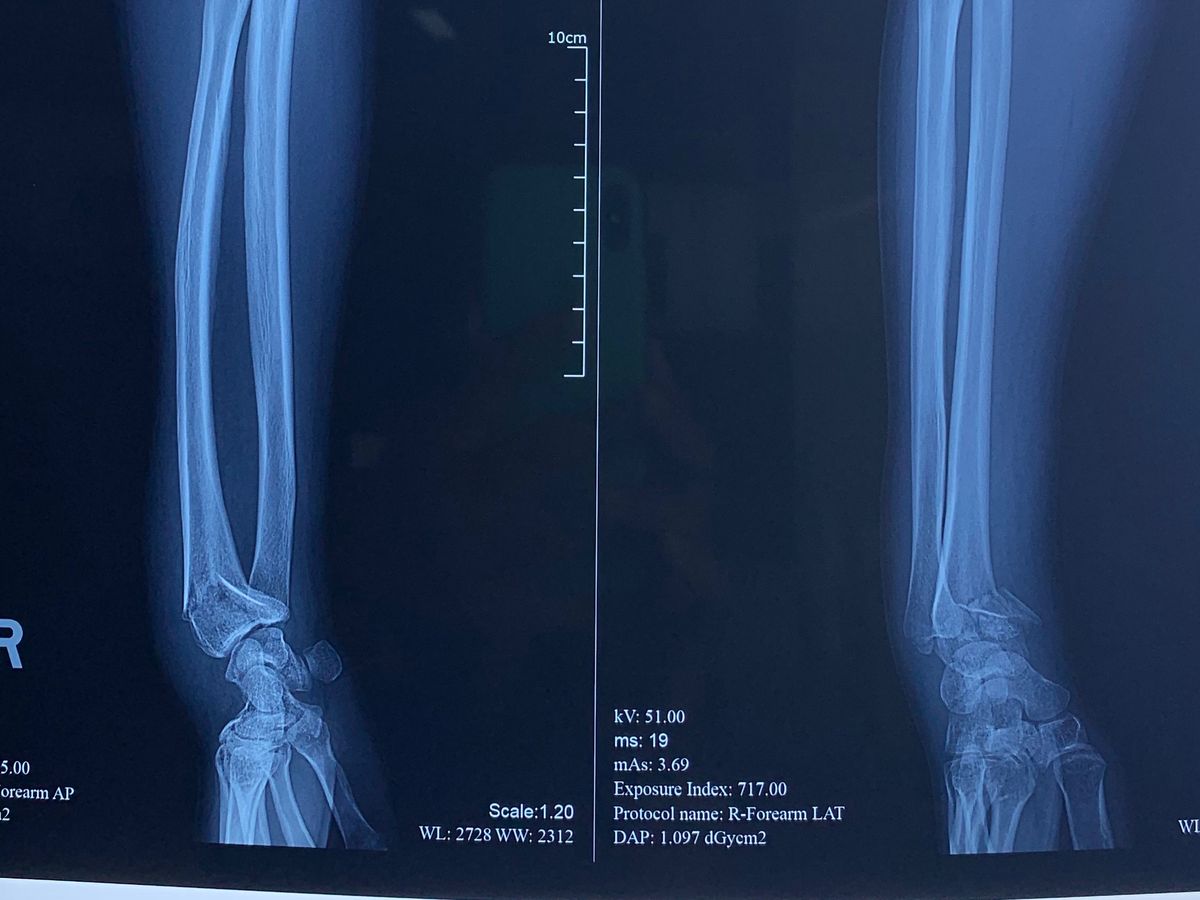

I got into an ATV accident yesterday morning which resulted in my wrist broken and fractured. I’m currently in Bali, Indonesia and it would be a risk to fly home right now without getting my wrist repositioned. I need to have an urgent procedure done to avoid long term issues. I found out about Travel Insurance while I was already on my trip, so I purchased it without knowing it had to be purchased before I left the US. The travel insurance won’t cover my expenses. I need to go under General Anesthesia and have it reset. I’m asking for your help because I have pay for this out of pocket. If you would like to venmo me instead, my venmo is @hannahrs6 Prayers are also very welcomed. Thank you in advance ❤️